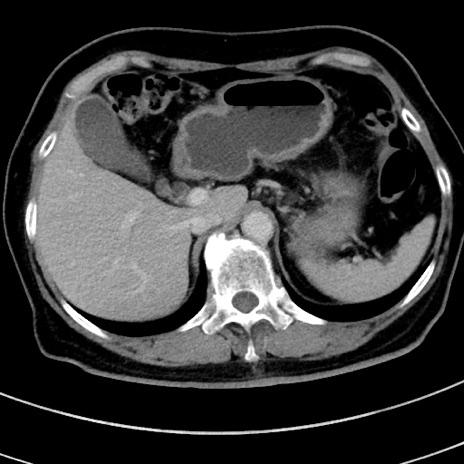

症例9(横断像)

【症例】 60歳代女性

【主訴】むかつき、みぞおちの痛み

【現病歴】3日前よりむかつきがあり、食事がとれない。

【既往歴】糖尿病

【身体所見】発熱なし、心窩部圧痛軽度あるも、腹膜刺激症状なし。

【データ】WBC 7400、CRP 1.92